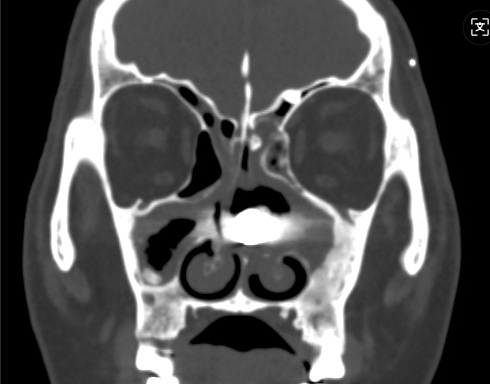

CT搜检印证了忖度:左侧鼻腔内真的有一高密度异物!